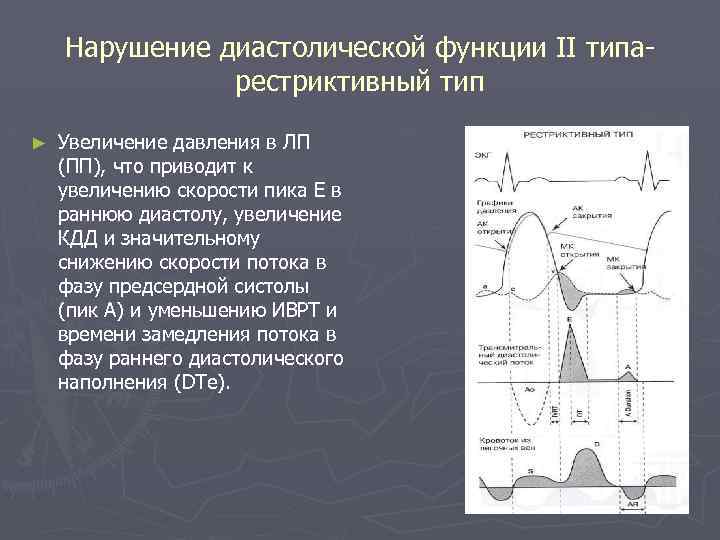

Нарушение диастолической функции II типаpестриктивный тип ► Увеличение давления в ЛП (ПП), что приводит к увеличению скорости пика Е в раннюю диастолу, увеличение КДД и значительному снижению скорости потока в фазу предсердной систолы (пик А) и уменьшению ИВРТ и времени замедления потока в фазу раннего диастолического наполнения (DTe).